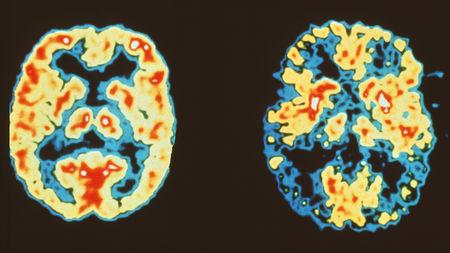

Brains without (left) and with (right) Alzheimer’s disease; Figure courtesy Science Magazine

The diversity of human brain function may not be encoded within a constant genetic blueprint; neurons can reshuffle their genes, a new study published in Nature reveals. This modification of the neurons’ genetic architecture may increase the protein variety in the brain, but it may also be related to Alzheimer’s disease, the study suggests.